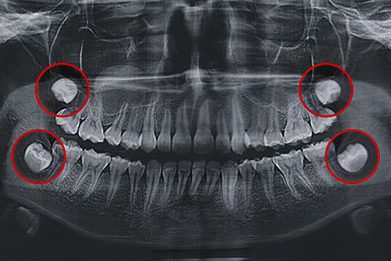

L’examen clinique et la radiographie panoramique dentaire permettent de suivre l’évolution des dents de sagesse et de poser l’indication de conserver ou d’extraire les dents de sagesse.